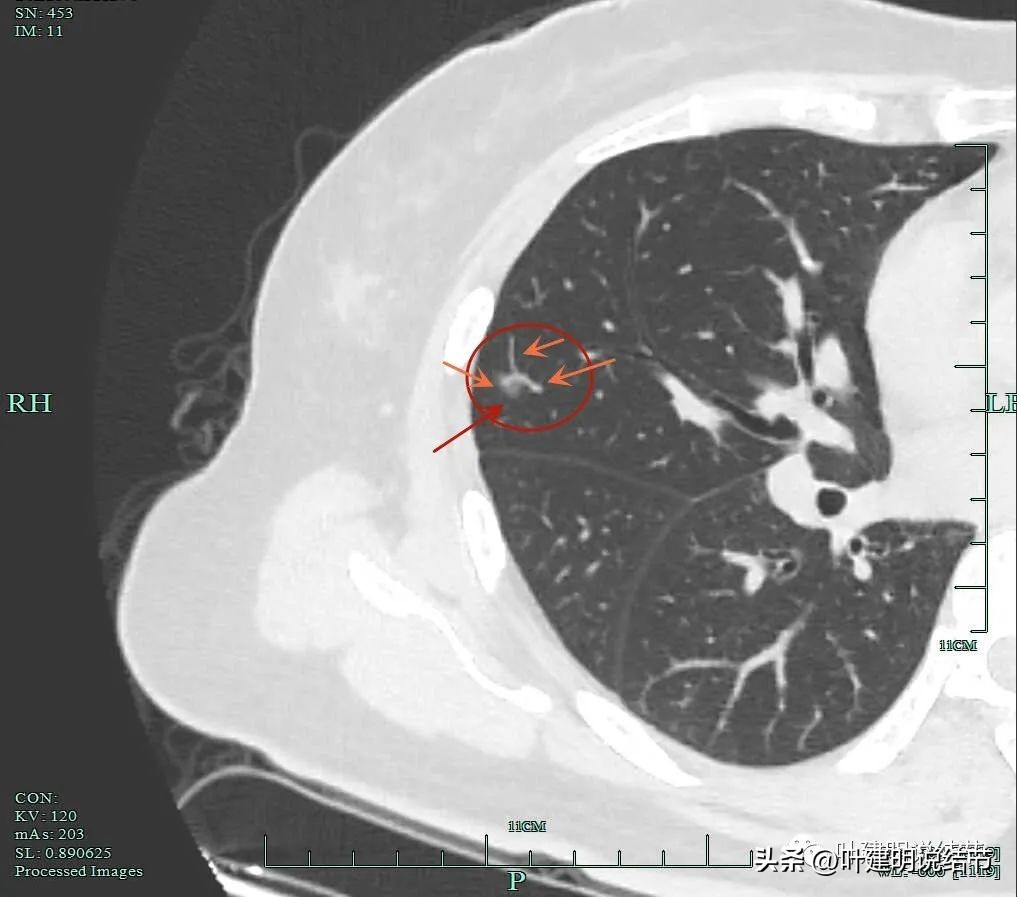

靶扫描重建图像显示了病灶明显的血管进入(如桔色箭头所示),灶内似见进入血管的穿行,而且显得毛糙与异常增粗。

微小血管进入明显且多处;粉色箭头示病灶内部偏实性成分也明显。

血管征以及磨玻璃成分,病灶轮廓与瘤肺边界清。我们见进入的这支血管是有异常增粗的,它不是越往远心端越细,而且基本同样粗细走向病灶,到了病灶内部后显得散开来,密度反而更显高点。

血管进入,局部细毛刺样征,轮廓清楚。